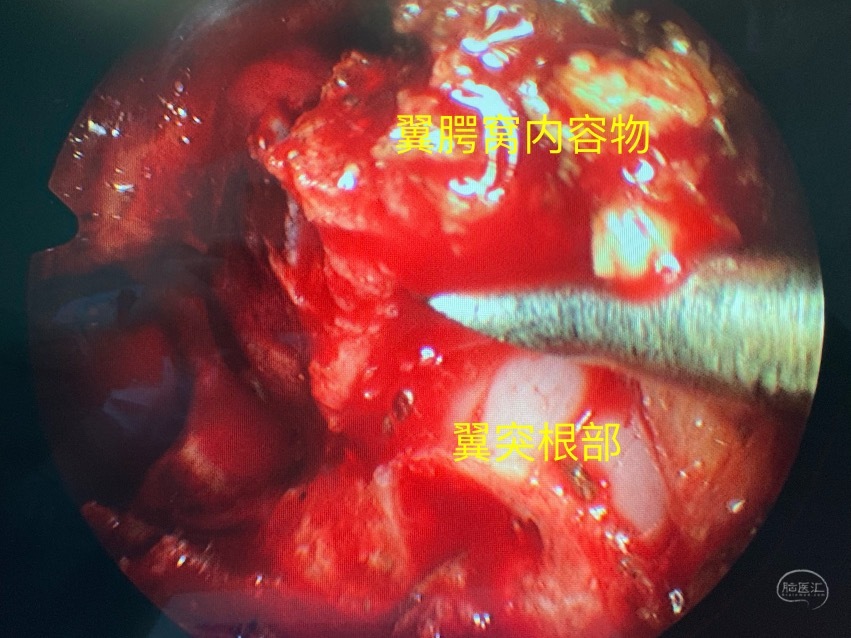

开放上颌窦后壁进入翼腭窝

将翼腭窝内容物移位显露翼突根部